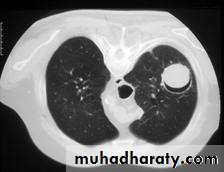

• @HRCT characteristically shows macronodules (usually ≥ 1 cm) Dense, well-circumscribed lesion(s) with or without a halo sign -Air crescent sign-Cavity@Culture or histopathological evidence of Aspergillus in diseased tissue gives a definitive diagnosis by bronchoscopy.

@detection of Aspergillus cell wall components in blood or BAL fluid, and Aspergillus DNA by PCR.